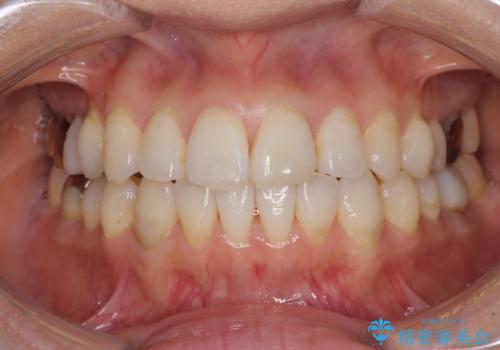

- 捻れた前歯と目立つ銀歯を気にして来院された患者様です。

歯列不正は軽微であったため、インビザライン・ライトにて改善することとしました。

インビザライン・ライトによる矯正治療であったので、時間をかけずに治療を終えることができました。

口を開ける度に目立っていた銀歯もセラミックで自然な口元の印象となりました。